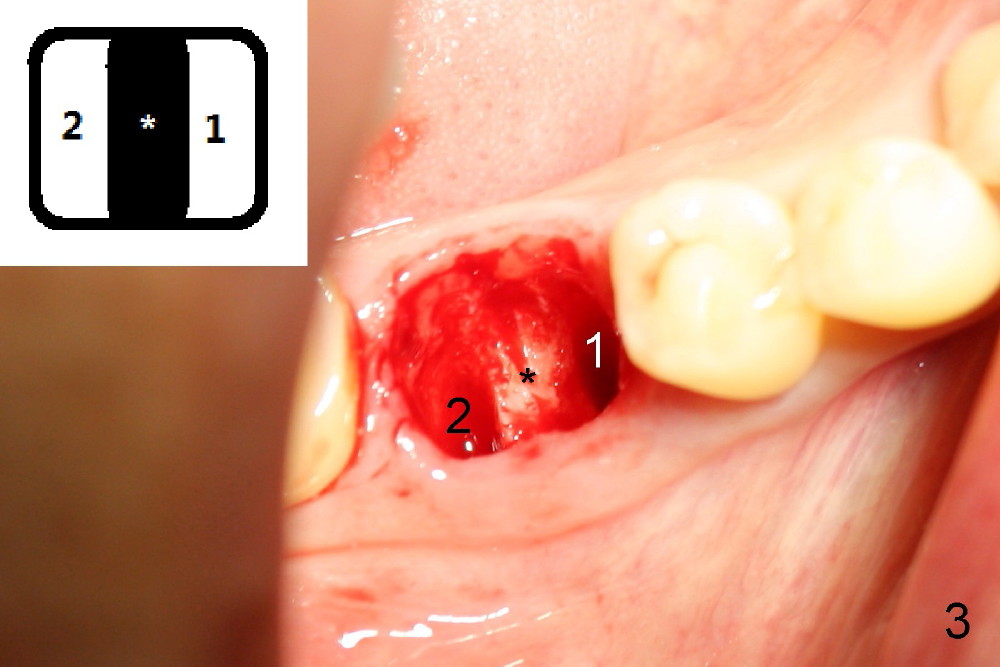

A sixty-year-old lady fractured the crown of the lower right first molar (Fig.1). The residual roots were sectioned (Fig.2 between arrowheads) and removed. The septum (Fig.3 *) is round on the top between mesial and distal sockets (1,2). Thin osteotomes (bone scalpel, bone blade; Fig.4: T) were used to section the septum mesiodistally. Fig.5 shows the sectioned septum, which makes it easy to insert round tapered osteotomes (Fig.5 inset green; Fig.6 R) without slipping either into the mesial or distal socket.